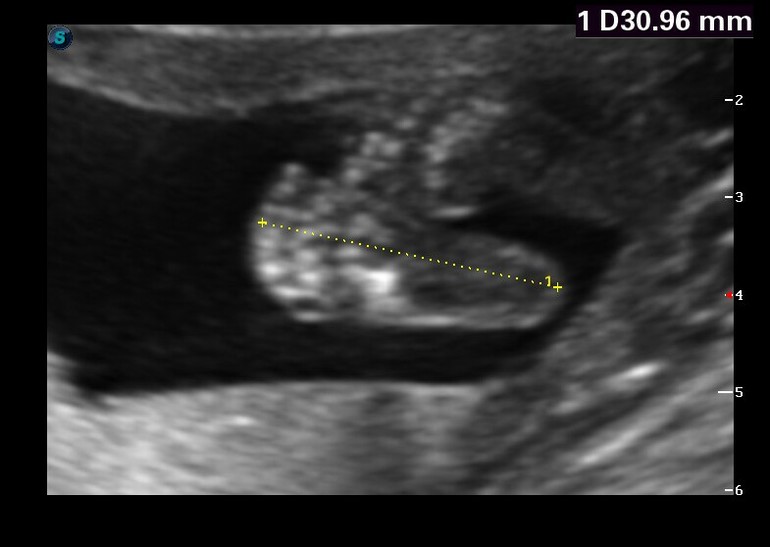

По УЗИ мы соответствуем срокам. Нас дядя доктор похвалил, малую, что развивается по срокам и очень активная, меня, что плацента высоко, шейка длинная и ни каких угроз нету))